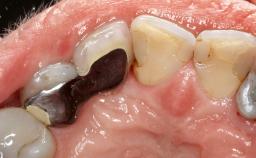

Peri-Implant Mucositis Associated with Misfit of a Cemented Restoration

A 37-year-old male patient was referred to the Department of Periodontology at the University of Bern, Switzerland, by a private dentist. Tooth 21 had been lost due to trauma and had been replaced with an implant and a cemented single crown. The tapered-effect tissue-level implant had a diameter of 4.1 mm, a length of 12 mm, and a sandblasted and acid-etched (SLA) surface (Straumann Dental lmplant System; Institut Straumann AG, Basel, Switzerland). The metal-ceramic crown had been cemented permanently, leaving a submucosal gap between the implant shoulder and the crown margin. Absence of marginal bone loss apical to the polished transmucosal neck of the implant could be observed .